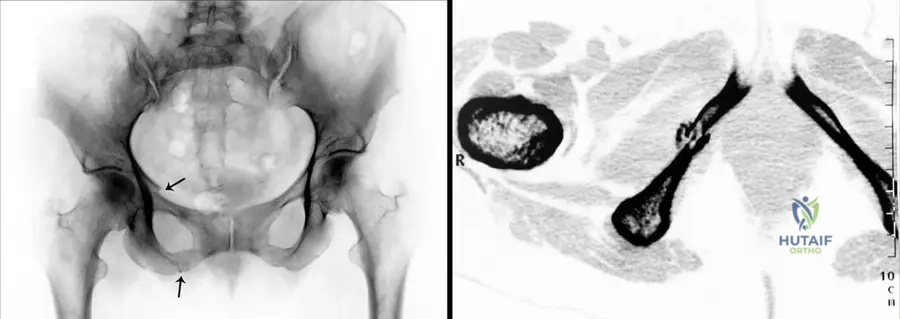

Question 38

A 3-year-old girl is diagnosed with a mesomelic dwarfism. Her parents are concerned about potential hip problems. On examination, she has short, malformed fingers and reduced elbow mobility. Radiographs show bilateral hip dislocations.

View Answer & Explanation

Correct Answer: D

Rationale: The text specifically lists "hip dislocation" as a feature of Acro–coxo–mesomelic dwarfism, which is distinct from the features listed for Nievergelt and Langer type. While "reduced articular mobility of elbows" is mentioned for Acro-coxo-mesomelic, "deformities of the elbow joints" is listed for Nievergelt/Langer, making hip dislocation a clearer distinguishing feature.

A genetic counselor is discussing the prognosis and recurrence risk for a couple whose child has a form of mesomelic dwarfism. The child presents with hip dislocation, clubhand, and short malformed fingers, and genetic testing reveals an autosomal recessive inheritance pattern.

Rationale: The text describes Acro–coxo–mesomelic dwarfism as "autosomal recessive dwarfi sm, with hip dislocation, clubhand and foot, short malformed fi ngers, reduced articular mobility of elbows, clinodactyly, brachyrhizophalangia." This matches the clinical picture and inheritance pattern in the vignette. Nievergelt's and Langer types are autosomal dominant.